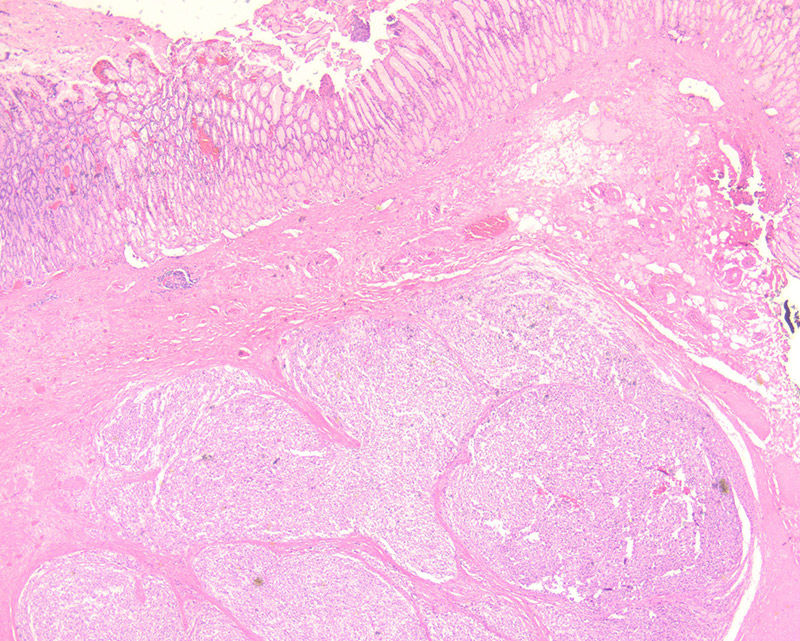

Initial laboratory work up demonstrated that the patient was anemic (Hgb = 4.5 g/dL), with WBC and platelet count within normal limits. CT scan revealed two exophytic masses originating from the greater curvature of the stomach at the antrum with intra and extraluminal components (Figure 1). Upper endoscopy noted a few small, smooth sessile polyps in the gastric antrum. One large ulcerated polyp was noted close to the pylorus.

The polyp was non-obstructing and not actively bleeding; biopsies were taken of this polyp. Histologically the biopsy specimen demonstrated a proliferation of uniform mixed epithelioid and spindle-epithelioid cells amongst antral-type mucosa (Figures 2, 3). No significant pleomorphism or mitotic figures were identified. Immunohistochemical stains for DOG1 and c-Kit (CD117) were positive (Figures 4 and 5, respectively). A subsequent wedge resection of the stomach to include the lesions was performed and confirmed the original biopsy diagnosis (Figure 6). Molecular testing for c-Kit and PDGFRA were performed and were negative.